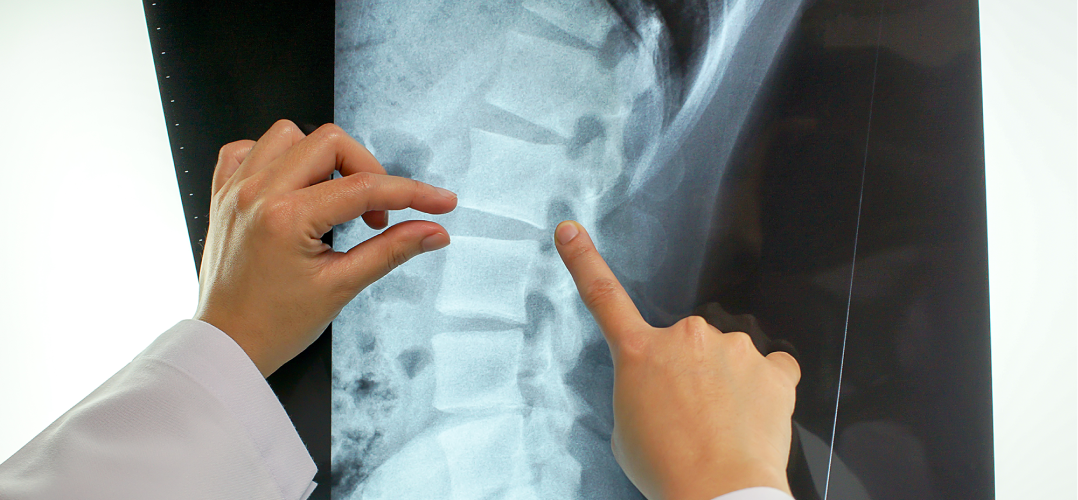

경추부의 전반적 구조를 볼 수 있습니다.

디스크의 경화 상태, 인대의 석회화, 경추 뼈의 구조를 볼 수 있습니다.